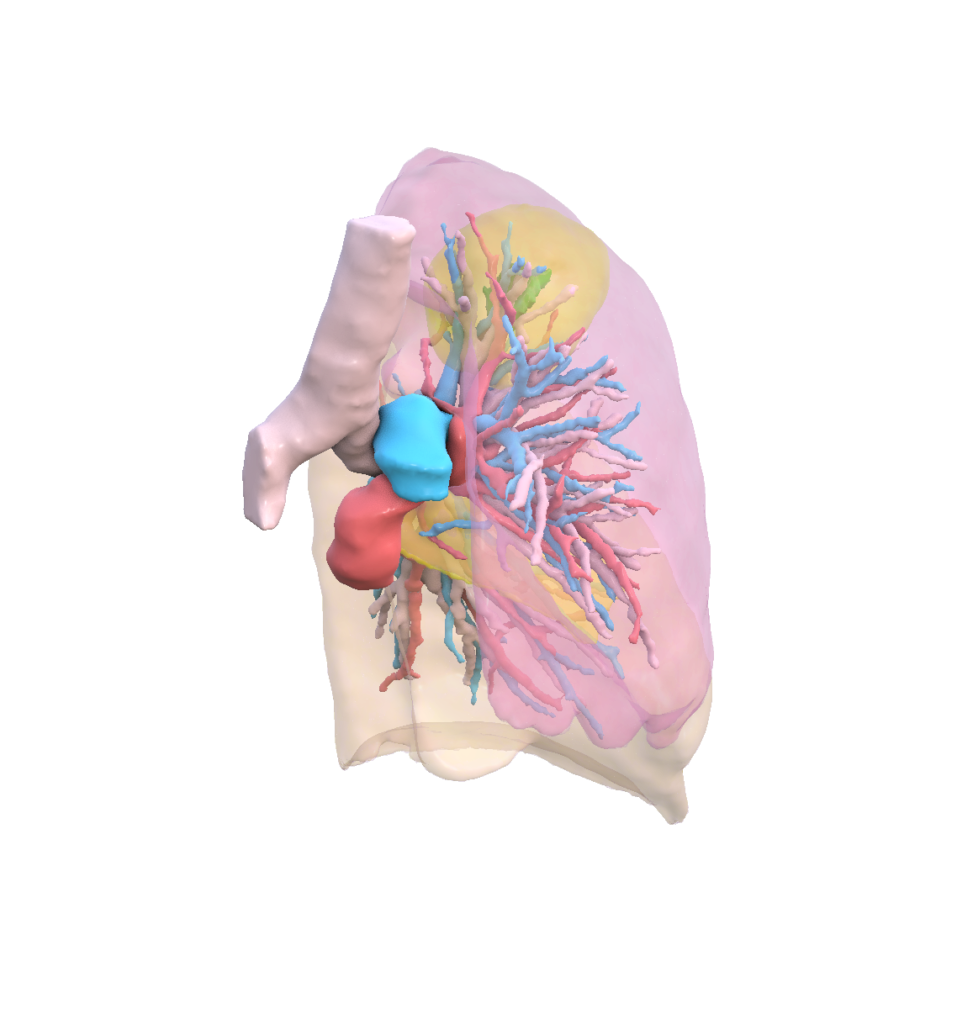

Our mission is to unlock the full potential of medical imaging data by transforming clinically validated CT and MRI images into high‑fidelity, synthetic digital human twins—enabling trustworthy, scalable, and privacy‑preserving AI development for healthcare.

To extend Visible Patient Lab’s clinically validated 3D anatomical expertise into synthetic digital human twins, enabling safe and effective AI innovation without compromising medical accuracy or patient privacy.